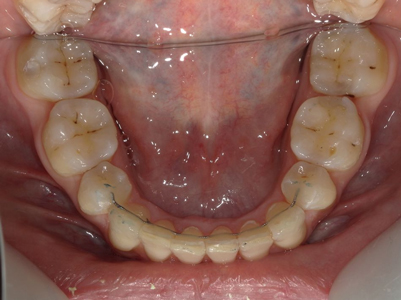

Arcade mandibulaire avant traitement orthodontique, séquelles de maladie parodontale

Après traitement orthodontique et réalisation d’une attelle fibrée (courtoisie Dr Patrick Fournier)